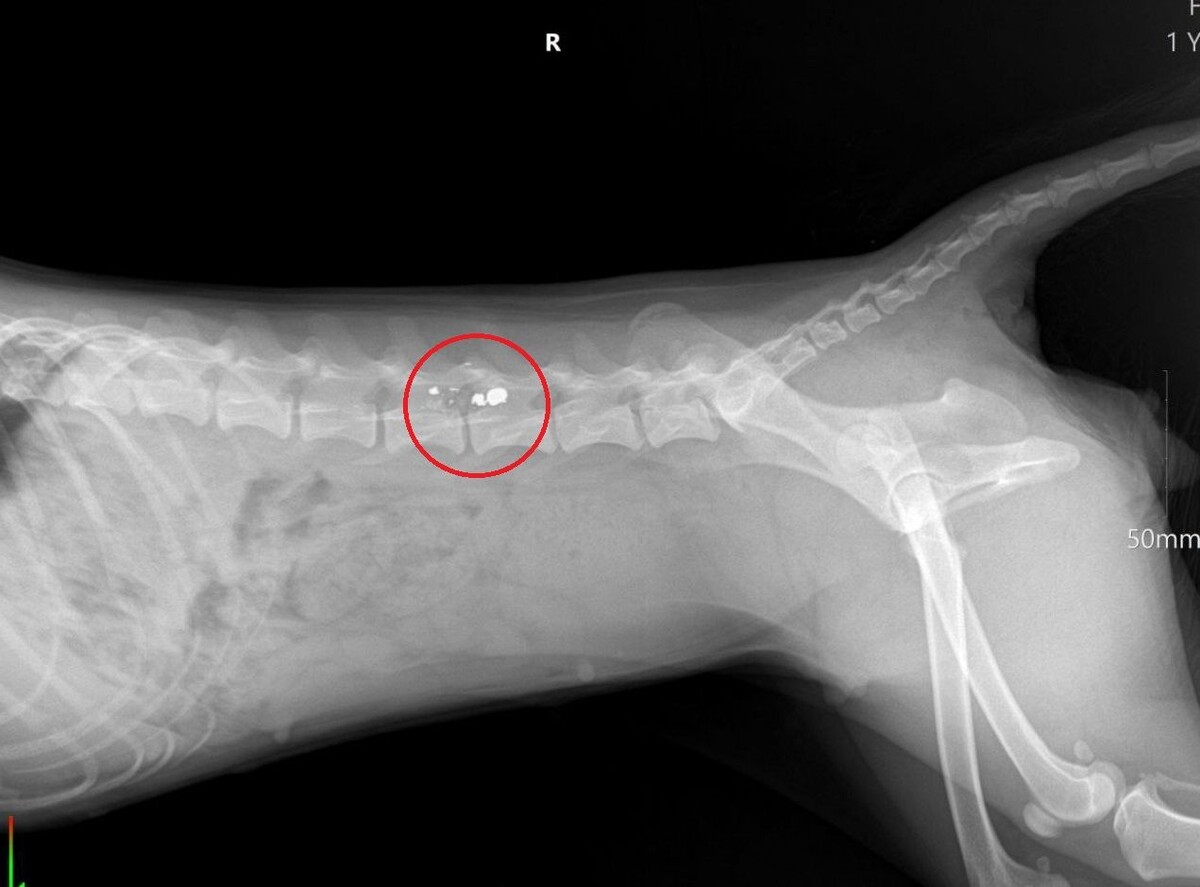

Мужчина выстрелил в собаку из винтовки. Инцидент произошел на глазах у детей в селе Горнозаводском в конце октября, сообщили в пресс-службе ГУ МВД России по Ставропольскому краю. 45-летняя хозяйка животного отвезла его в ветклинику. Врачи диагностировали травму, которая привела к отказу задних лап. Полицейские задержали стрелка. Им оказался местный житель. Он пояснил, что пес не раз душил его кур, свободно гулявших по улице. Посчитав его за бездомного, мужчина выстрелил в него. Правоохранители завели на сельчанина уголовное дело о жестоком обращении с животным. Вскоре фигуранта будут судить.

45-летняя хозяйка животного отвезла его в ветклинику. Врачи диагностировали травму, которая привела к отказу задних лап.